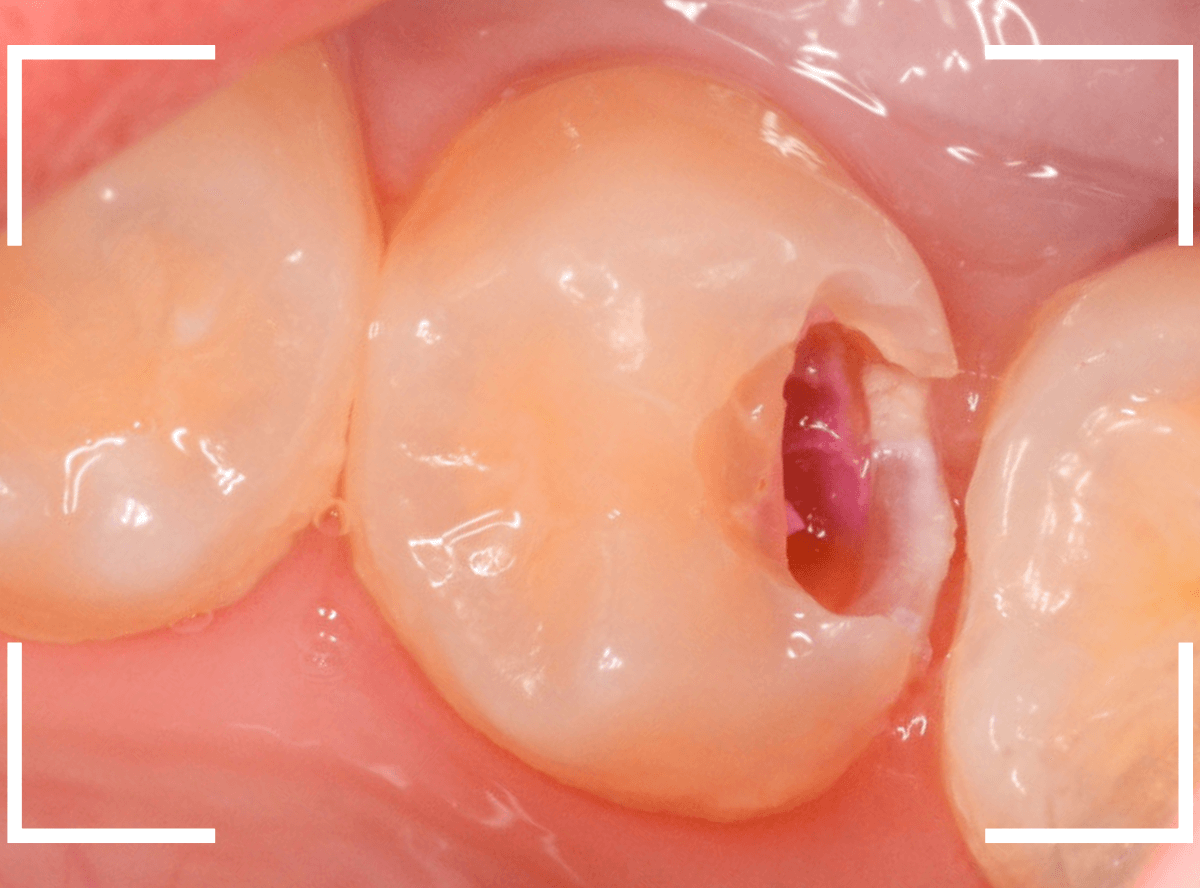

Case.19 神経まで達する大きな虫歯

「歯に違和感がある」という訴えで来院された患者さんです。

後ろの歯との間にぽっかり穴が開いているのがわかります。

このような場合、大抵は中で大きな虫歯になっています。

治療を開始します。

少し削ったら、予想どおり大きな虫歯が出てきました。

虫歯が深いので、いつも以上に慎重に治療をすすめます。

赤くう蝕検知液で染まっている部分が虫歯です。

やはり虫歯は大きく、歯の神経が一部露出する状況でした。

神経の中には血管もつまっていますので、出血するわけです。

神経を残せる可能性は半々といったところですが、神経を保護するお薬をつめた上にセメントで蓋をしました。

これでお痛みが出ないか、しばらく経過観察が必要です。